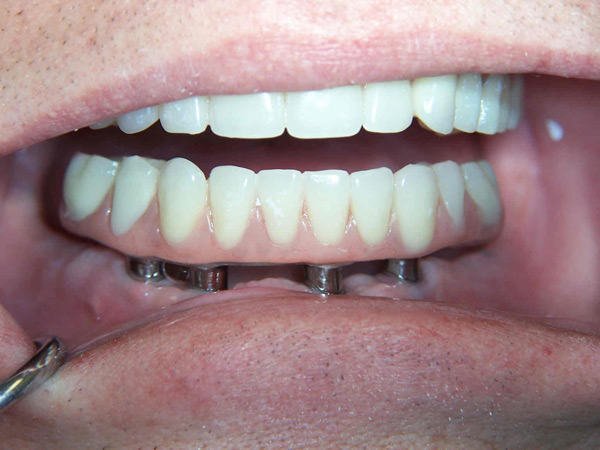

Problem: This patient presented with severe decay and a difficult occlusion/bite. He had teeth that had already been removed.

Plan: Our plan… remove the rest of the teeth and place an upper denture. Place four implants on the lower using guided surgery. Restore with a fixed/hybrid bridge.

A solution to every problem.